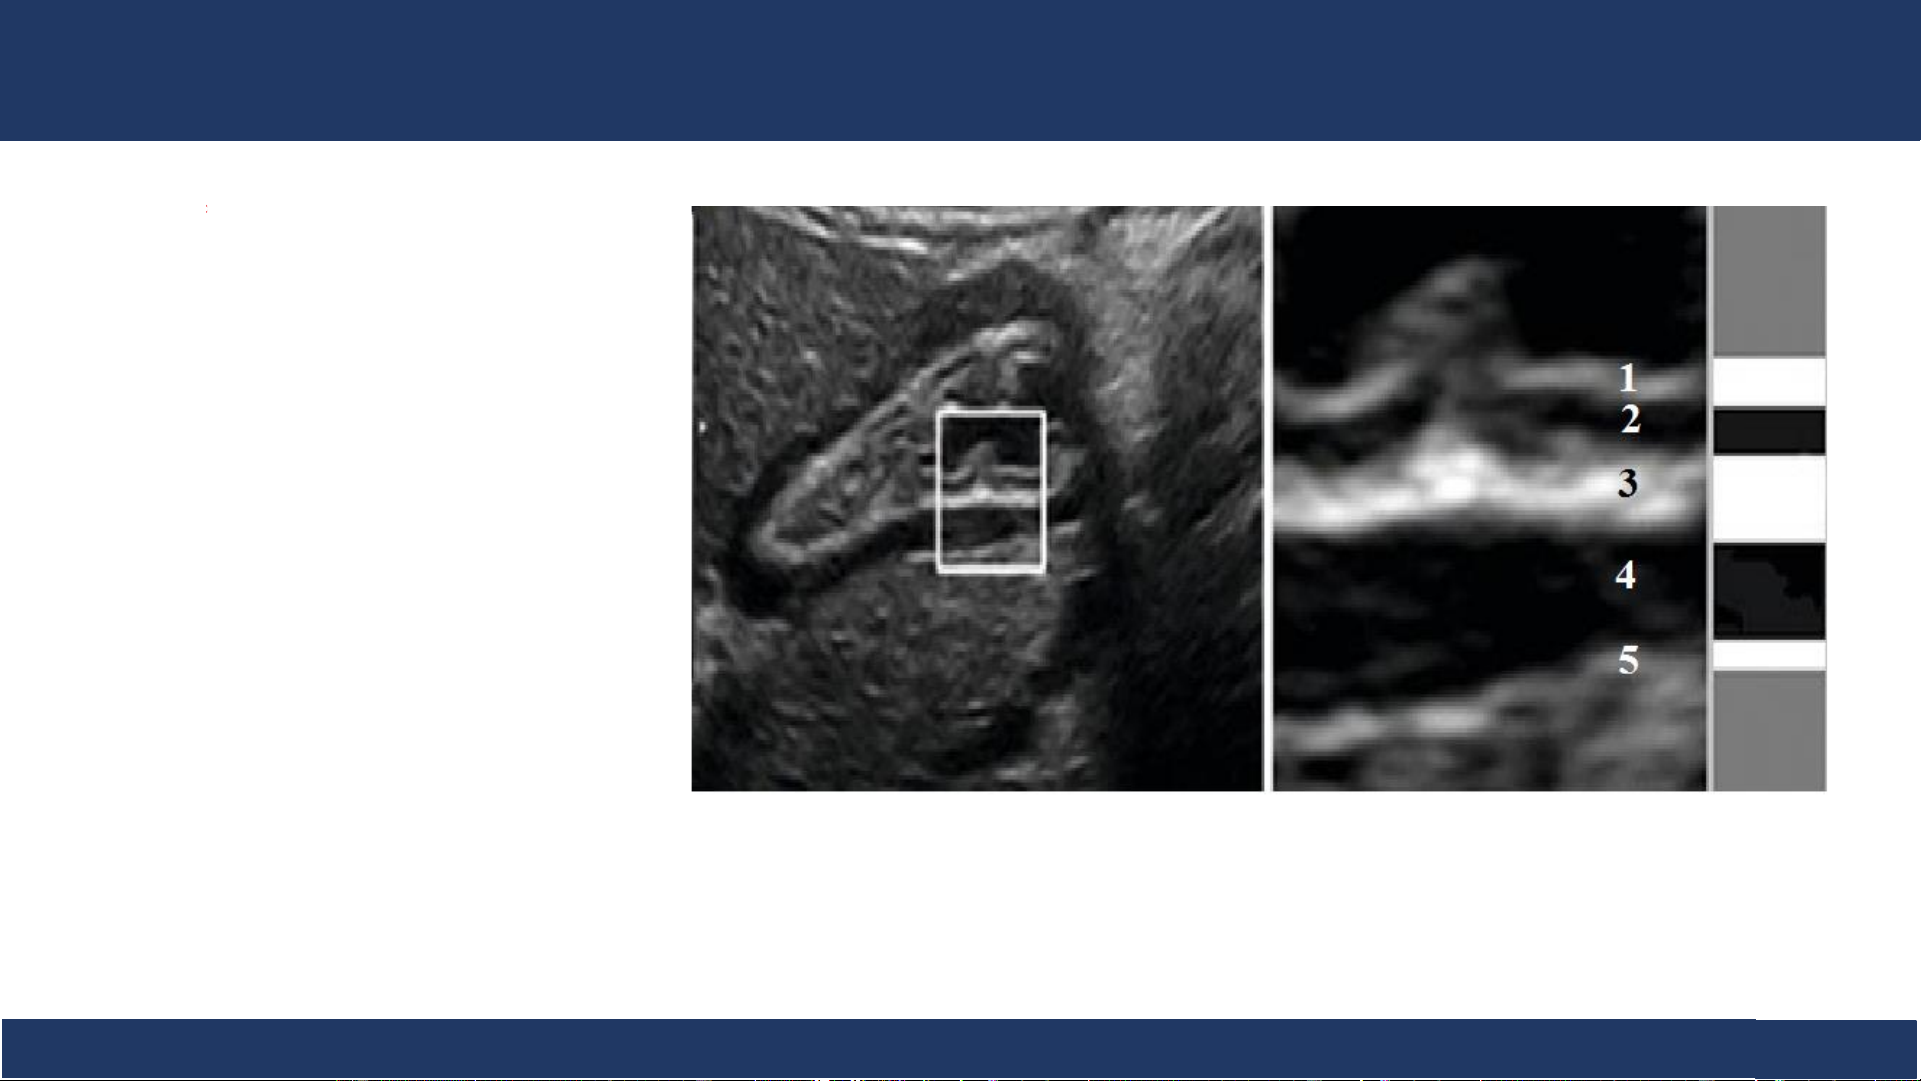

Trên siêu âm có thể thấy được 3-5 lớp:

• Niêm mạc phản âm dày • Cơ niêm phản âm kém

• Lớp dưới niêm phản âm dày • Lớp cơ phản âm kém

• Lớp thanh mạc phản âm dày. Bệnh v B iệ ộ môn n Nh Chẩ i Đồng n đoán 1

hình ảnh, ĐHYD TPHCM 7 Siêu âm 1. Niêm mạc 2. Cơ niêm 3. Lớp dưới niêm 4. Lớp cơ 5. Thanh mạc Bệnh v B iệ ộ môn n Nh Chẩ i Đồng n đoán 1